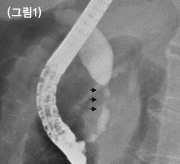

시술에 대해 간략히 알아보면 우선 내시경을 담즙이 십이지장내로 흘러나오는 부위인 유두부에 위치시킵니다. 카테타를 이용해 담도를 조영한 후 협착부위의 위치, 길이 등의 정보를 알아냅니다 (그림 1). 협착부위를 중심으로 플라스틱관 혹은 자가팽창성금속관을 상,하부에 걸쳐 위치시킵니다(그림 2-A, 2-B). 협착 정도에 따라서 풍선으로 먼저 협착부위를 확장한 후 상기 시술을 시행하기도 합니다. 기대여명이 3~6개월 이상인 악성종양환자에게 주로 자가팽창성금속관을 삽입하게 됩니다. 추적관찰기간 동안 스텐트 내부로 암세포가 자라 들어와 황달이 다시 발생하는 경우 다시 스텐트를 삽입할 수도 있습니다.악성종양에 의한 담도협착이 아닌 경우 즉, 수술 후 담도협착 (그림 3), 간이식후 담도협착, 원인불명의 양성담도협착, 원발성 경화성 담관염에 의한 담도협착 등의 경우에도 담도배액술을 시행하는데 대개 이 경우에는 제거가 가능한 플라스틱관을 삽입하며 때에 따라서는 여러 개의 플라스틱관을 오랜 기간 동안 삽입하는 경우도 있습니다 (그림 3-A, 3-B). 담석제거 후 잔여담석이 남아있는 경우 혹은 담관염 예방 및 치료 등의 경우 내시경을 이용하여 얇은 관의 한 쪽 끝을 담도 내에 위치시키고 다른 한 쪽 끝은 코를 통하여 체외로 위치시켜 이 통로를 통해 담즙을 배액하는 ‘내시경적경비담도배액술’을 시행하기도 합니다.

췌장암으로 인해 담도가 협착되어 있으며(검정화살표) 이로인해 담도가 확장되어 있는

사진입니다. 자가팽창성금속관을 담도협착부위에삽입한 직후에 찍은 사진, 협착으로 인해 좁아져 있는

췌장암으로 인해 담도가 협착되어 있으며(검정화살표) 이로인해 담도가 확장되어

있는 사진입니다.